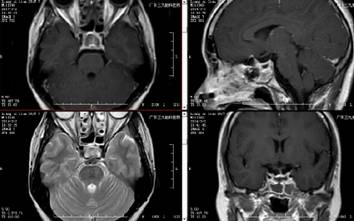

■ 术后

术后复查头颅CT、MRI示:呈术后改变,垂体脓肿消失。复查内分泌检查提示:皮质醇(COR)130.36pg/L,垂体催乳素(PRL)36.856ug/L。患者术后症状明显改善,内分泌症状改善,出院3个月后随访,患者未诉明显不适,一般情况好。